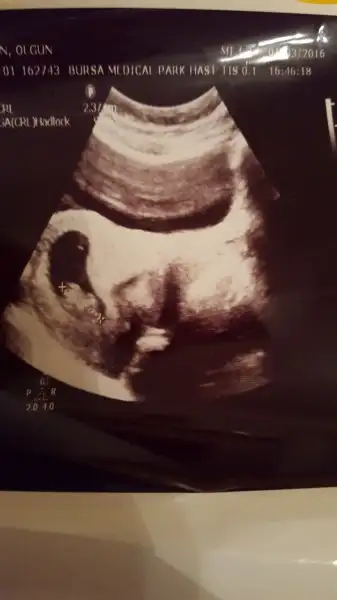

Ben de bi cinsiyet tahmininizi alırım işte miniğimin ilk resmi :KK46::KK46::KK46:

Bu da benim fasulye.. cinsiyet tahmini istiyorum ben de.. :)